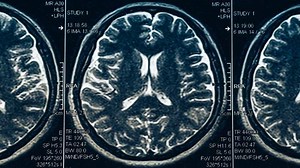

Seizures Lead to Pediatric Brain S…